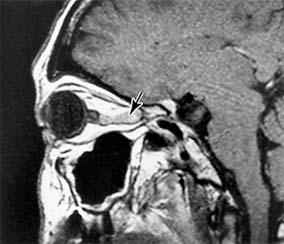

Figure 14-18

Figure 14-18: Axial MRI of sphenoid wing meningioma causing proptosis.